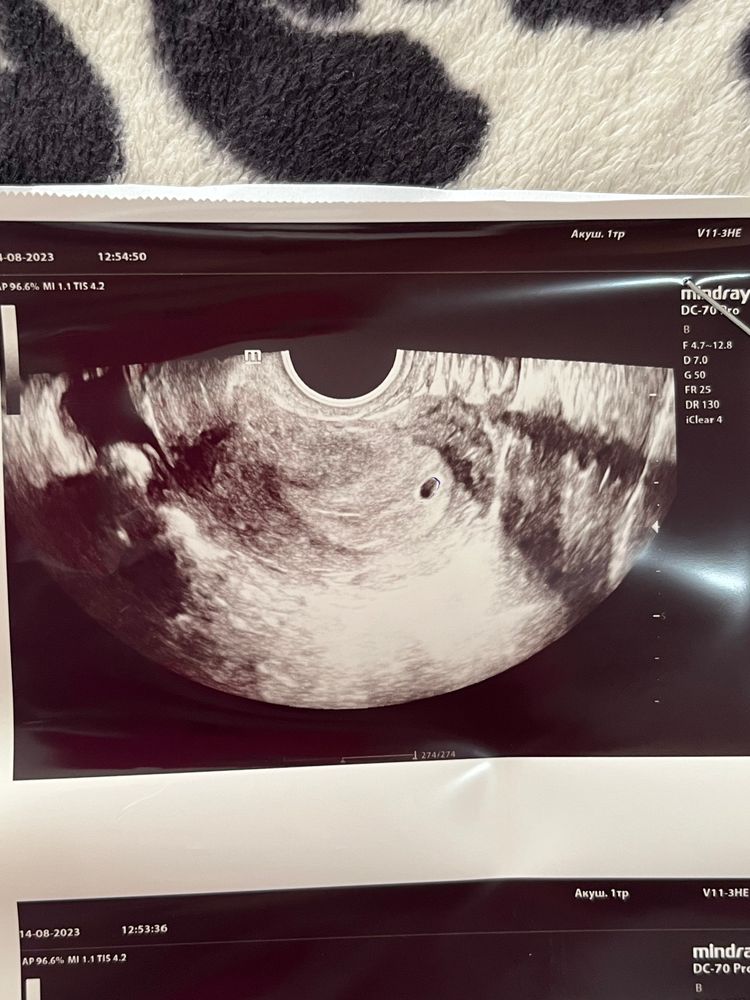

Ну что ж девочки, сходила я на первое узи на 7 день задержки. 4 недели эмбр.ПЯ 0,6см . Врач сказала что оно неправильной формы, гематома, отслойка 8 мм, и вообще угроза и вообще все плохо, назначила фолиевую, снова сдать завтра хгч и повторное узи через неделю. Хочется плакать. ..

Честно, погуглила кучу картинок, не поняла, что не так с формой пя.. овальное, красивое, с желточным мешочком вроде даже

Не знаю, по моему нормальное ПЯ, что врачу там не понравилось, не пойму🤷🏼♀️ вроде такое ровненькие и красивое...

Не расстраивайтесь, пя и должно быть такой формы, если бы оно было сплющенное,тогда да, а так все отлично у вас🤗